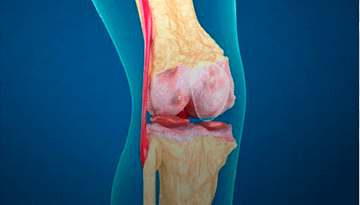

хрящевой ткани

сустава и постоянная боль

изуродованные конечности

Боль и хруст в суставах, отеки и покраснения — это симптомы серьёзных проблем. Без своевременного лечения эти болезни становятся причиной полной потери подвижности и необратимой деформации суставов

«Заболевания опорно-двигательного аппарата – это всеобъемлющая проблема, с которой сталкивался практически каждый житель нашей Страны. Только остеоартрозом на сегодняшний день болеют 12% жителей Таджикистана независимо от возраста. Опасность таких болезней заключается в том, что они приводят к полной инвалидности. К счастью, несколько лет назад ведущими мировыми специалистами был разработан натуральный крем под названием Arteron. Как показала наша практика, применение крема Arteron позволяет избавиться от отечности, воспаления и боли в суставах и полностью восстановить их функции в домашних условиях всего за 2 недели...»